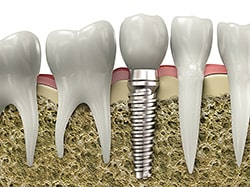

An implant is a synthetic tooth root in the shape of a post that is surgically placed into the jawbone. The “root” is usually made of titanium: the same material used in many replacement hips and knees, and a metal well suited to pairing with human bone.

A replacement tooth is fixed to the post. The tooth can be either permanently attached or removable. Permanent teeth are more stable and feel more like natural teeth.